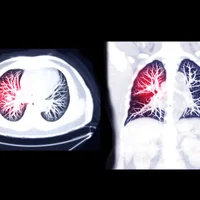

Diagnostic : le diagnostic de la pneumonie peut être posé à l'aide de plusieurs méthodes, notamment :

• Radiographie thoracique pour visualiser les zones affectées des poumons.